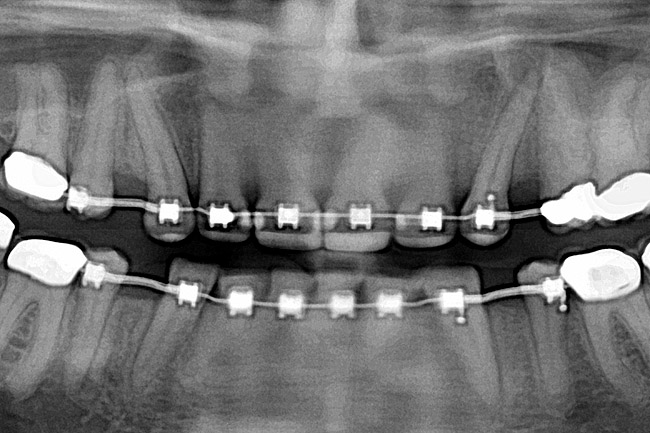

Fig 12 (and Fig 13). Incisors were too upright and had severe incisal wear. He was concerned about esthetics of the worn teeth and his insufficient lip support. Progress photo and panorex 9 months after corticotomies were performed on Nos. 6 through 11. Previous extraction sites were reopened orthodontically to improve function and fill lip support. Incisal edges were restored provisionally with composite resin. Note that despite the creation of adequate spaces to replace missing teeth, there is inadequate room for placement of dental implants because of severe tipping of all the anterior teeth. Osteotomy SFOT may have been a better choice because it would have allowed needed alveoloskeletal correction (without excessive tipping) instead of the primarily dentoalveolar correction common in corticotomy SFOT. Restorative dentist: Brad Jones, DDS.

Figure 12

Fig 13 (and Fig 12). Incisors were too upright and had severe incisal wear. He was concerned about esthetics of the worn teeth and his insufficient lip support. Progress photo and panorex 9 months after corticotomies were performed on Nos. 6 through 11.

Figure 13